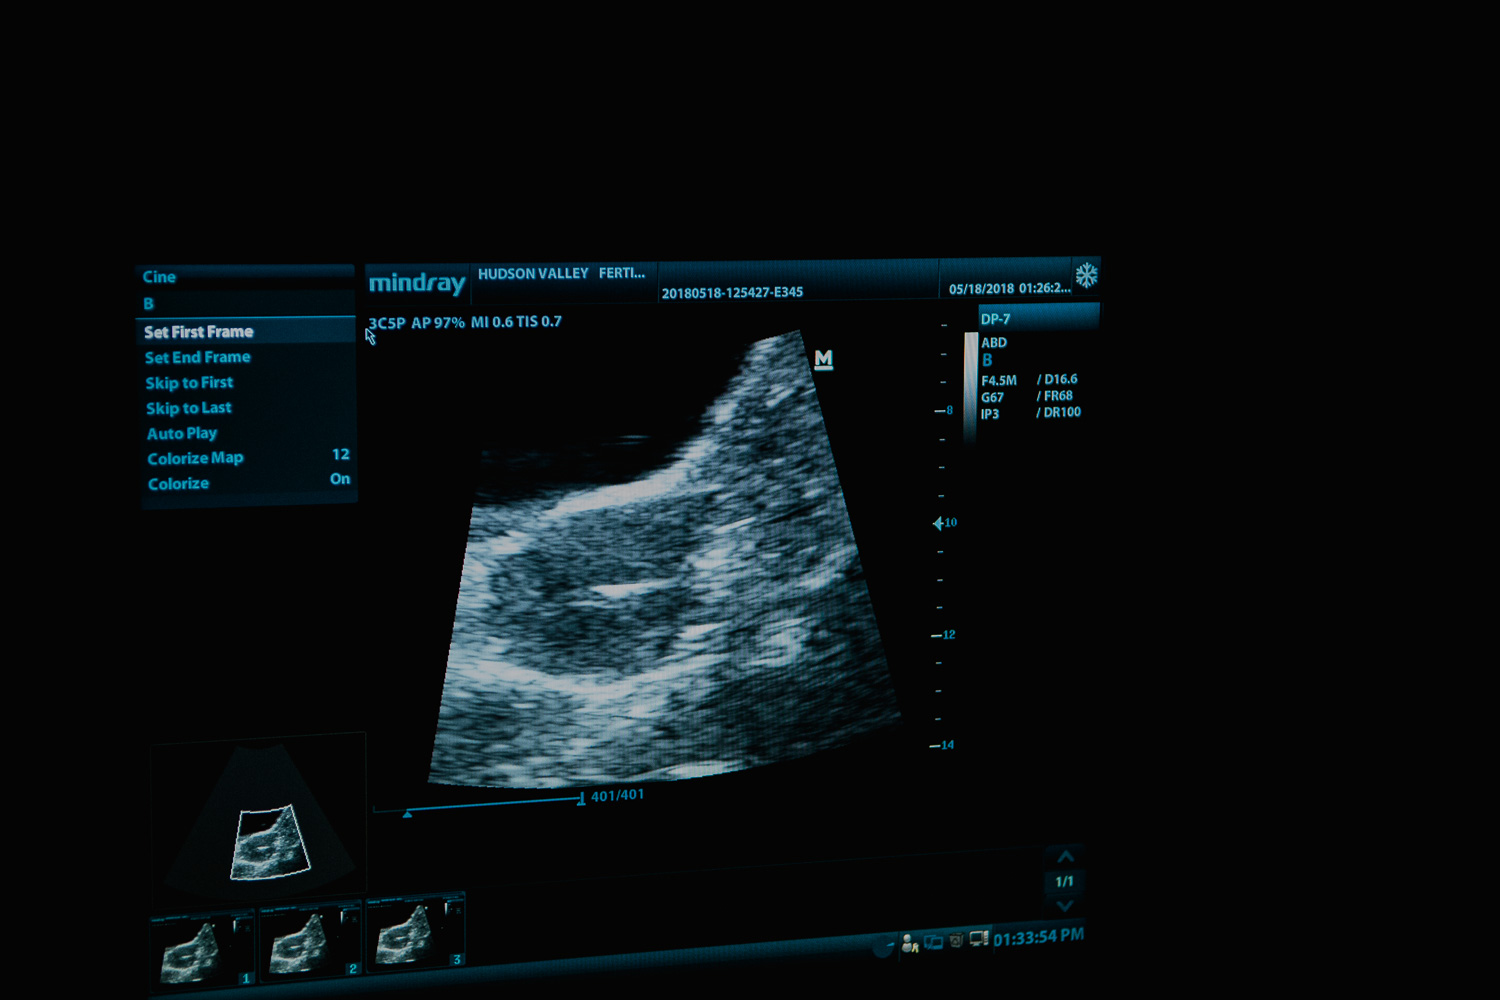

May 19, 2018

Kerri's transfer was canceled. Then rescheduled. Then canceled. And then rescheduled, and HAPPENED yesterday (May 18, 2018!

We arrived at 11:30am for a 12:00pm transfer. And as of 12:34pm they conceived! The transfer was a success!

An extra special thank you to Dr. Levine of Hudson Valley Fertility and his staff for allowing me to cover this story with the most intimate coverage.